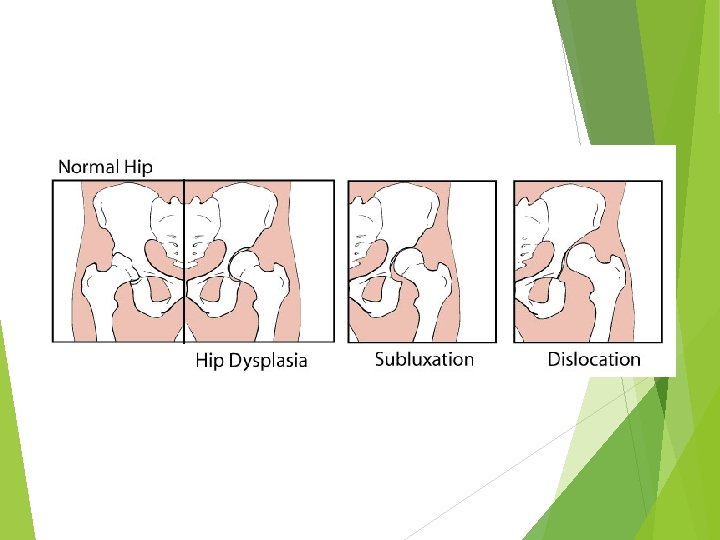

DDH a spectrum of disease that includes dysplasia : shallow or underdeveloped acetabulum subluxation : displacement of the joint with some contact remaining between the articular surfaces dislocation : complete displacement of the joint with no contact between the articular surfaces